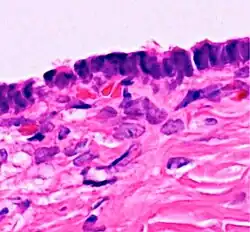

![]() |

Lepromatous leprosy | Skin biopsy showing epidermal atrophy and multiple dermal infiltrates. | Category: Histopathology of leprosy | Leprosy |